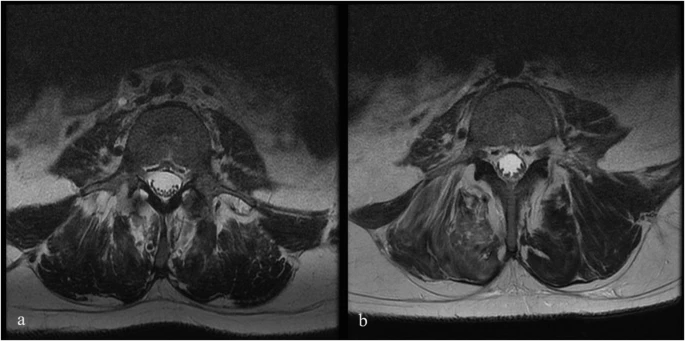

注射后血液和腦脊液檢查未發(fā)現(xiàn)異常。隨訪時(shí)MRI未見(jiàn)明顯變化;然而,在十名患者中,有八名檢測(cè)到馬尾神經(jīng)根的叢集輕度增加,有或沒(méi)有結(jié)節(jié)性增強(qiáng)的證據(jù)。在經(jīng)歷馬尾神經(jīng)根聚集或強(qiáng)化的患者中,沒(méi)有發(fā)現(xiàn)明顯的臨床相關(guān)性。圖1顯示了患者6的輸注前和隨訪MRI,該患者L4-S1水平的馬尾神經(jīng)根叢集輕度增加。表3突出顯示了所有患者干細(xì)胞注射前后的MRI變化。三名患者的SSEP有所改善。兩名患者與基線相比沒(méi)有任何變化,四名患者無(wú)法進(jìn)行解釋,一名患者在整個(gè)研究期間具有正常的SSEP。表4突出顯示了SSEP 的發(fā)現(xiàn)和解釋。